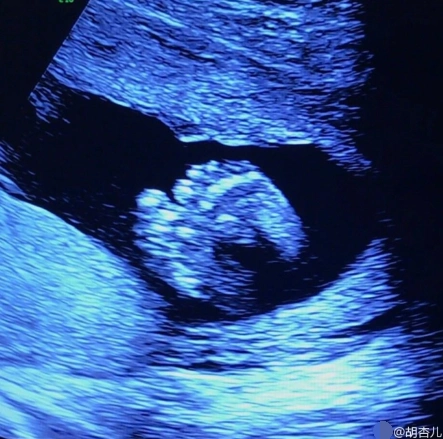

胡杏儿晒胎儿b超照 宝宝小脚丫超可爱(图)